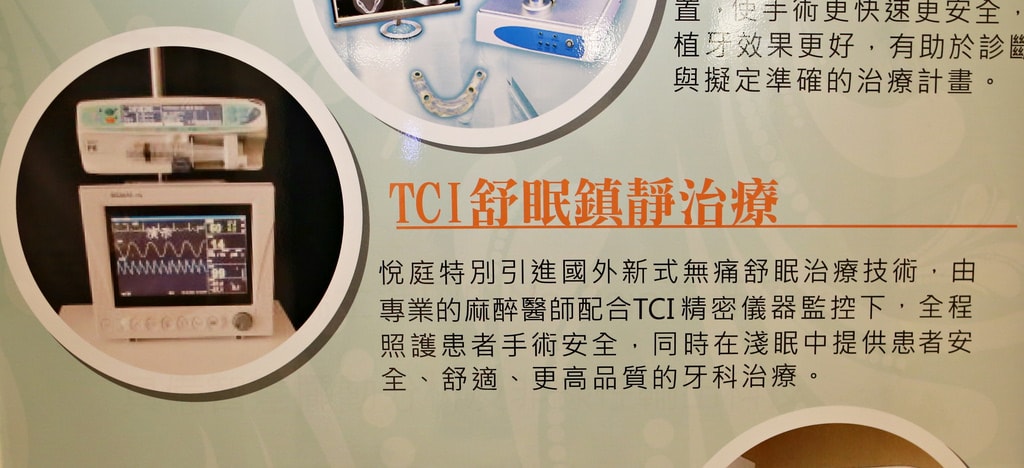

讓我最感興趣且來活動的原因之一>>「無痛舒眠治療-TCI舒眠牙醫鎮靜治療」

就是這台TCI精密儀器與生理監測儀

無痛舒眠治療就是可以在淺眠的狀態下完成整個治療及手術

不是全身麻醉那種喔,淺意識還是聽得到醫生的指示

操作的會是由專業的麻醉醫師配合TCI精密儀器監控下,全程照護患者手術安全

適合的人—>看牙容易血壓飆高或心跳加速、有心律不整問題或高齡者,或是令你感到害怕的牙齒手術皆可

像我就是屬於心跳加快,我一進去就開始快了然後躺上去根本就是時速200在跳(笑)

不適合的人—>肝腎功能、心肺功能或呼吸道疾病重度異常者,吃雞蛋或花生過敏者,年紀大於90歲或小於2歲,孕婦

適用的治療—>人工植牙、牙周病手術、拔智齒、拔牙、磨牙、根管治療等,沒有任何限制